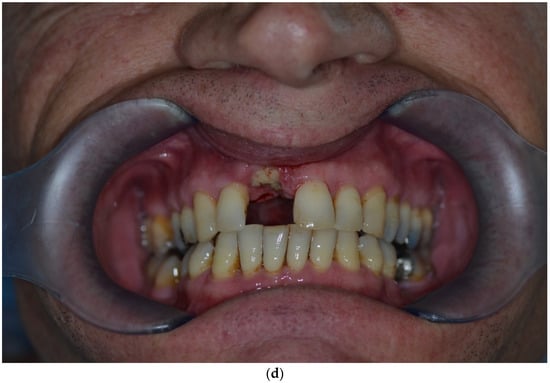

Over-contouring was defined as an over-augmentation of the alveolar process beyond the extent of the adjacent bone level (Figure 1). The reason for over-augmenting the alveolar process is often an anticipated shrinkage of the bone substitution material during the healing phase. Two patients were selected as examples to illustrate the term “over-contouring”. Patient 1 showed a Class III defect in the maxilla, and the alveolar ridge augmentation performed for correction was over-contoured (Figure 2). Patient 2 also showed a Class III defect in the maxilla, but the alveolar ridge augmentation performed for correction remained at the level of the surrounding bone (Figure 3).

Figure 3.

Clinical example of no over-contouring. (a) Class III defect with pronounced vestibular deficit and minor vertical deficit. (b) Attachment osteoplasty with a cancellous allogeneic bone block. The block fits into the contour of the surrounding alveolar process (within the envelope). The lining with the bovine granules is visible (vestibular opaque line). Cranially, the bone block ends at the bone border of the adjacent teeth.